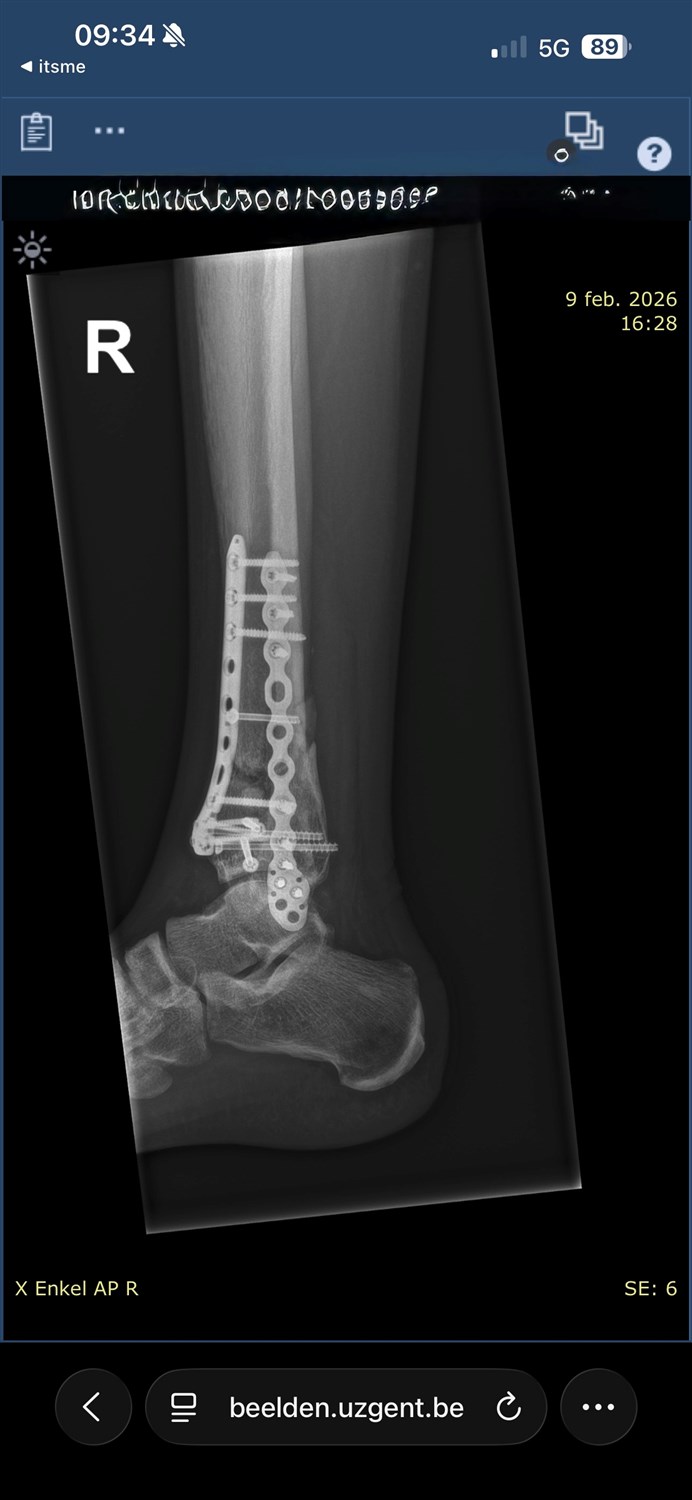

In November 2025 is ons leven plots drastisch veranderd. Een val van 8 meter heeft alles stilgezet. Hij brak beide voeten en liep zware schade op aan zijn ruggengraat. Sindsdien is niets nog van zelfsprekend.

Zware operaties, het herstel dat nog steeds aansleept. En de pijn... die die is er elke dag. Vooral zenuwpijn is moeilijk uit te leggenaan iemand die het niet voelt, maar ze stopt gewoon niet. Het kruipt onder de huid en laat je niet los!

Voor de medische kosten die blijven komen. Voor operaties die nog gepland staan. D rolstoel die nog moet komen. Voor de nodige aanpassingen die er moeten gebeuren thuis om alles leefbaar te maken en toegankelijk. En om door deze moeilijke en zware periode te geraken.